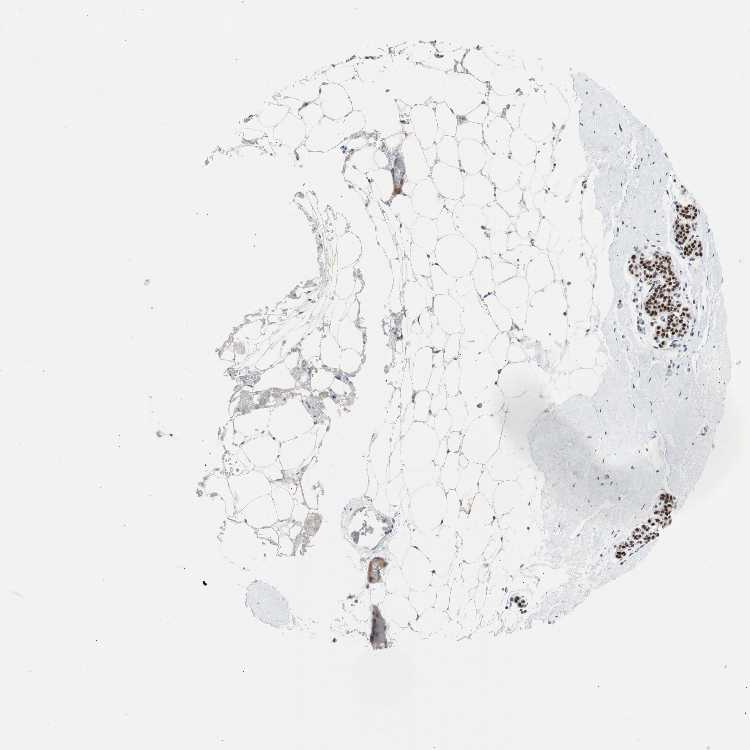

BREAST - Antibody stainingi

Antibody staining in the annotated cell types in the current human tissue is reported as not detected, low, medium, or high, based on conventional immunohistochemistry profiling in selected tissues. This score is based on the combination of the staining intensity and fraction of stained cells.

Each image is clickable and will lead to virtual microscopy that enables deeper exploration of all samples and also displays staining intensity scores, fraction scores and subcellular localization as well as patient and tissue information for each sample.

Antibody HPA006723Antibody CAB080348

Adipocytes HighMedium

Glandular cells HighHigh

Myoepithelial cells HighHigh